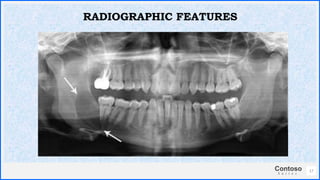

17

RADIOGRAPHIC FEATURES

ENVELOPMENTAL

COLLATERAL

REPLACEMENTAL

EXTRANEOUS

18

RADIOGRAPHIC TYPES